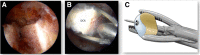

Arthroscopic distal clavicular autograft (DCA) is effective in shoulder instability with glenoid bone loss. The original technique uses an osteochondral autograft, fixed with screws or suture anchors. We developed a modified procedure called "congruent arc DCA" characterized by (1) use of drilling guides to optimize graft positioning and make the all-arthroscopic procedure safer and reproducible; (2) rotation of the DCA of 90° to reach a congruent arc with its undersurface; (3) fixation of the graft with cortical buttons to simplify its intra-articular passage, avoid hardware problems, and facilitate possible revision surgery; and (4) intraoperative use of a suture tensioner to achieve satisfactory compression of the graft and increase its consolidation.